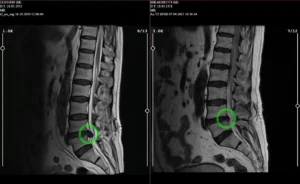

Ameliyatsız Bel Fıtığı Tedavisi

Cerrahi müdahaleye gerek kalmadan bel fıtığına etkili ve güvenli çözümler sunuyoruz